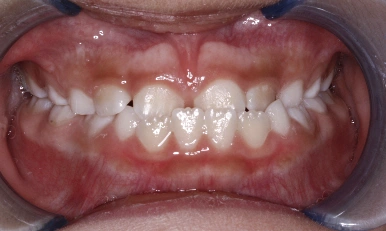

Patient Results